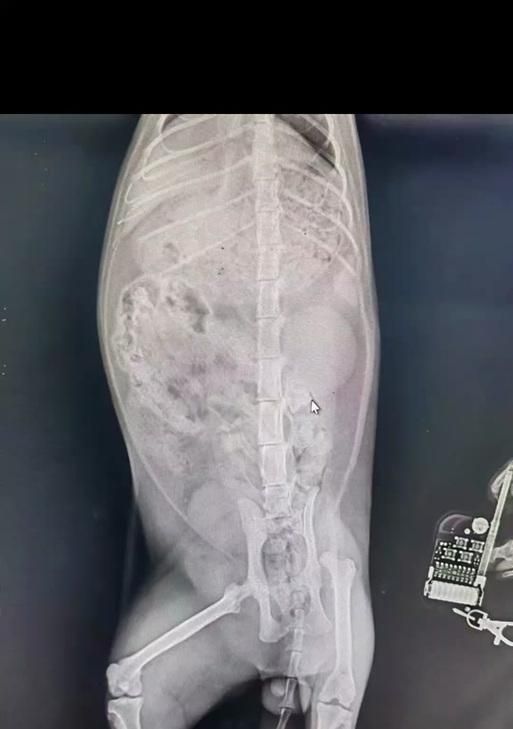

尾巴位置异常

猫的尾巴正常情况下应该挺直,但当发生脱臼时,尾巴往往会出现位置异常的情况,弯曲或者向一侧倾斜。

尾巴无法移动

正常情况下,猫的尾巴是可以自由移动的,但当发生脱臼时,尾巴会变得僵硬,无法进行正常的运动。

尾巴肿胀或变形

在尾巴脱臼后,受伤部位可能会出现肿胀或者变形的情况,需要及时观察。